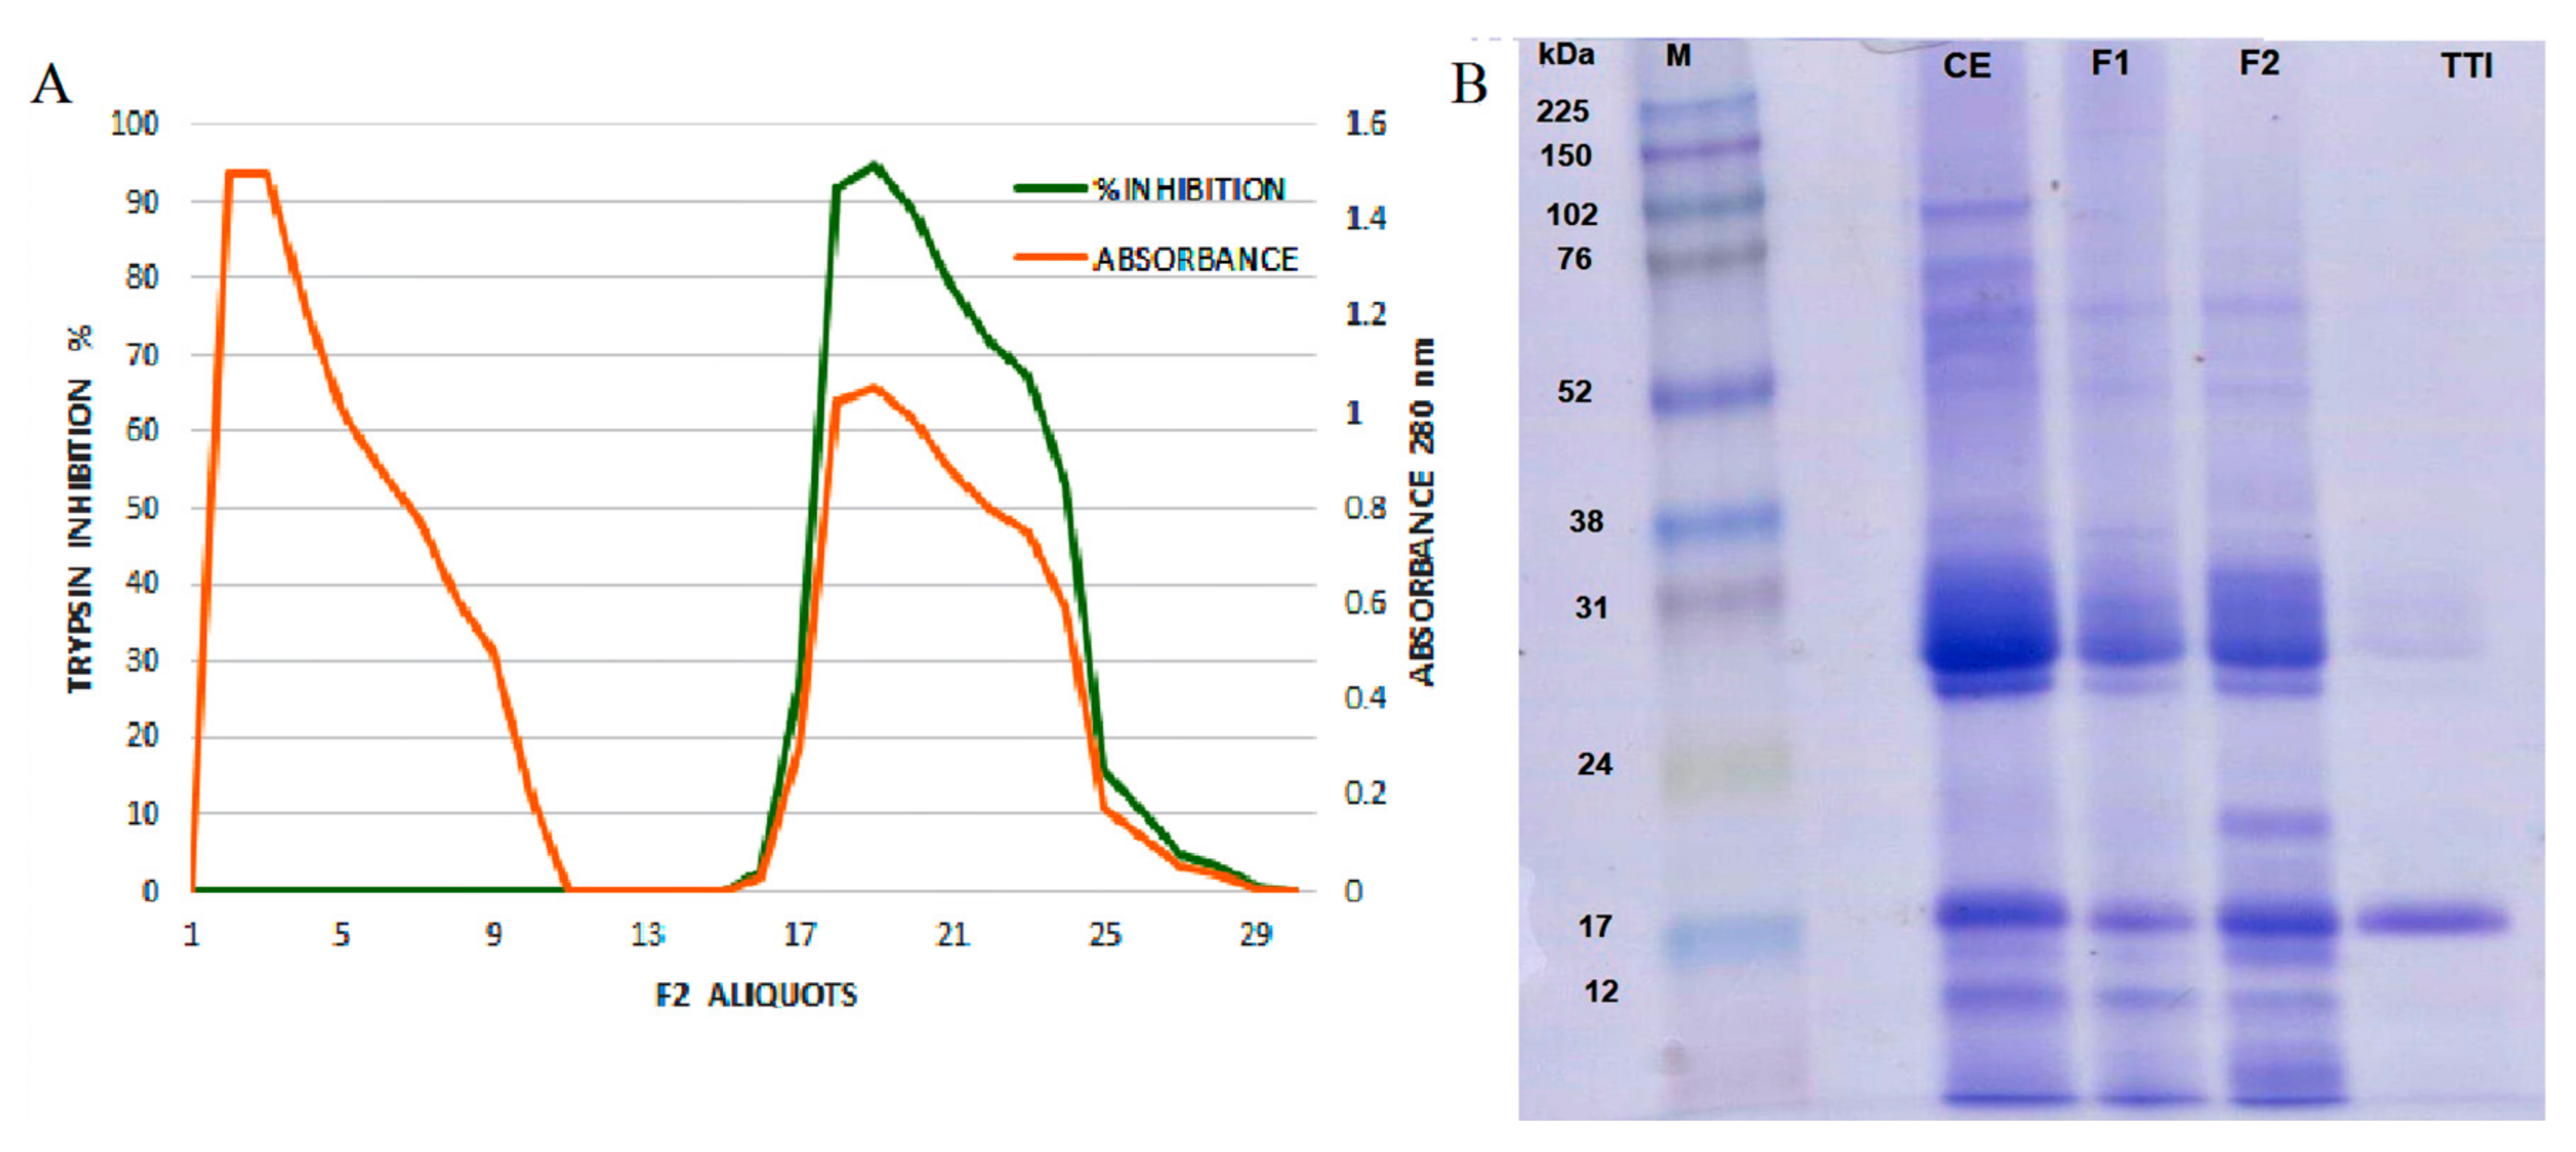

3.1. Tamarind Trypsin Inhibitor (TTI) Extraction and Quantification

3.2. Characterization of the Nanoformulations Obtained (CW and ECW)